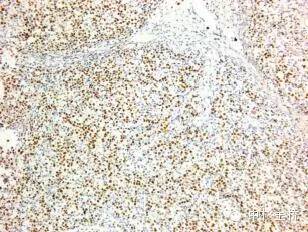

圖為EBER原位雜交染色DBA顯色,蘇木素復(fù)染